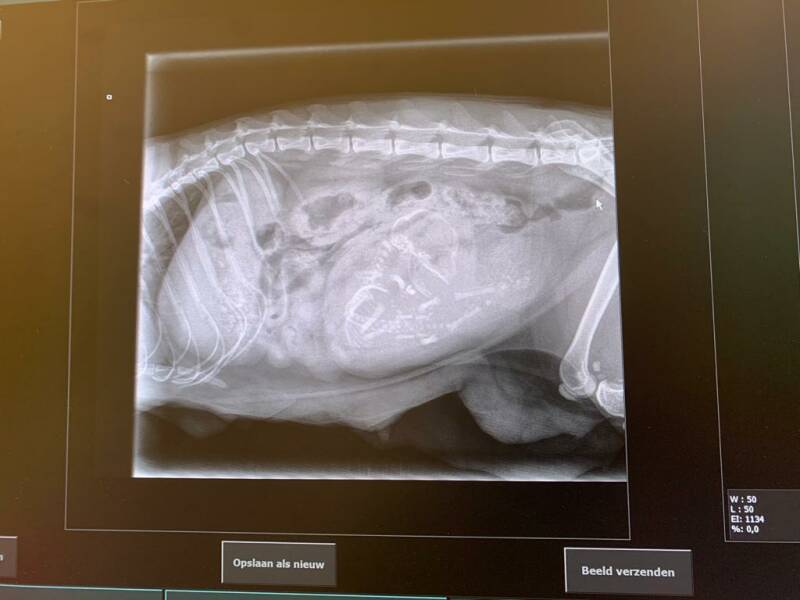

Lois was rustig en wilde koste wat het kost beneden zijn dus moeder en dochter naar beneden gebracht. Ze was gelukkig goed gegroeid en woog deze morgen al 80 gram. Lois vond dat ze nog meer verplichtingen had namelijk het voeden van Chanel haar kittens. Verder was rustig en heb een uur lopen voelen of er nog een kitten in zat. Er was nog beweging en na overleg met onze dierenarts deze ochtend besloten toch een foto te maken.

Onderweg in de auto naar de dierenarts, kitten ligt naast haar en ze is gelukkig heel rustig.

Het kitten lag er raar bij en was nog niet ingedaald en leek vrij groot op de foto. Besloten vanwege de stand en dat het nog niet was ingedaald in te grijpen dmv een keizersnede.

We moesten haar bij onze dierenarts achter laten want ze waren nog met een operatie bezig. Om 13:13 uur belde onze dierenarts en bleek ze ook een baarmoederontsteking te hebben, alles moest er gelijk uit. Lois is dus net als Chanel gesteriliseerd. Het kitten leeft gelukkig nog en ze doen het goed. We mogen haar zo ophalen (gelukkig). Het geslacht, kleur en gewicht weten we nog niet dat bekijken we wel als we thuis zijn. Nu snel naar onze dierenarts in Schagen.